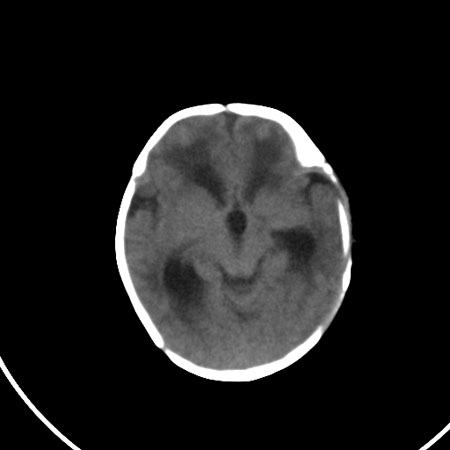

以下是引用小初学者在2009-1-10 17:51:00的发言:[br]考虑缺血缺氧性脑病后遗性改变。

以下是引用拾荒者在2009-1-10 19:23:00的发言:[br]生后有蛛网膜下腔出血病史,现幕上脑室明显扩张,脑室周围白质局限性密度减低,考虑hie脑病后遗表现。